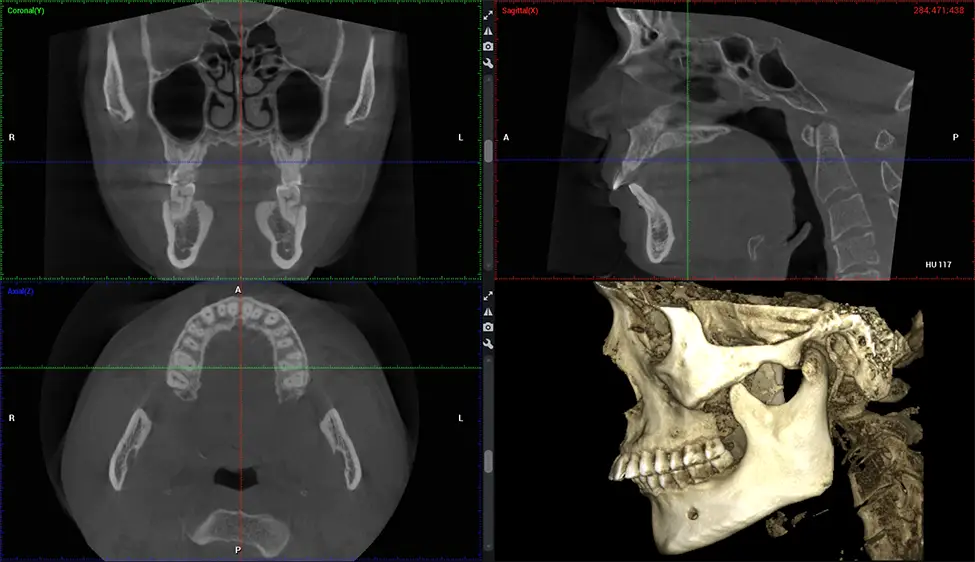

Cone Beam Computed Tomography (CBCT) is an advanced imaging technique used in dentistry and maxillofacial surgery to obtain detailed 3D images of the oral and maxillofacial structures. At Dr G Dental Studio, our CBCT scanners utilize a cone-shaped X-ray beam and a specialized detector to capture images from different angles. A computer then combines these images to create a 3D representation of the patient’s oral anatomy.

There are many benefits to using CBCT technology, especially compared to the traditional 2D X-ray format. One of the most significant advantages of CBCT scans is that they provide much more information than traditional X-rays. A scan lets your dentist see images from all angles of your jaw and mouth, including your sinuses, nasal cavity, cheekbones, and other surrounding areas. This added information helps your dentist craft a comprehensive treatment plan that addresses all aspects of your oral health.

Planmeca Viso G7 CBCT ( Cone Beam CT Scan ) is designed to surpass the demands of industry leaders, specialists, and large institutions. It’s has a large ø25×30 cm sensor with four built-in cameras. It can capture unlimited volume sizes from a ø3×3 cm to a ø30x30cm volume capturing the skullcap through C7 on the cervical spine. The Planmeca Viso G7 offers the industry’s largest single volume scan of ø30×19 cm. It’s poised to handle advanced imaging modalities such as Planmeca ProFace® and Planmeca 4D™ Jaw Motion technology. The occipital head support allows an unimpeded view of facial tissue.